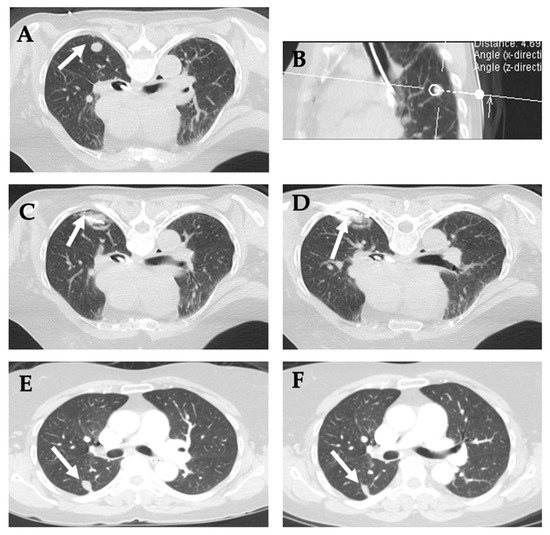

10. Primary and Metastatic Lung Tumors